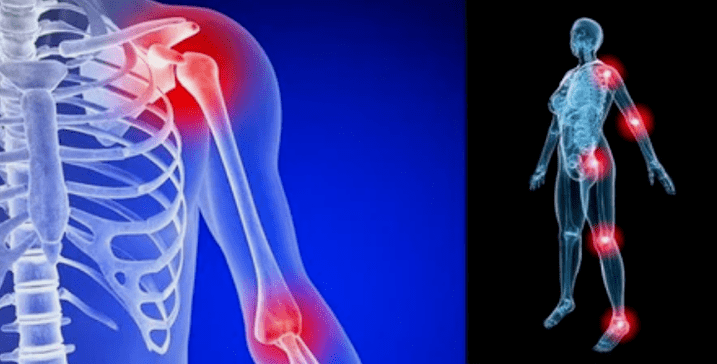

Disease manifestations differ slightly depending on localization, more often signs are reflected in the knees, shoulders and hooks, due to high loads.

- Pain.They have low weight in the initial phase, and the deterioration of the sensation condition is amplified.In the beginning, the joints were injured only after they woke, after light heat, the sensation disappear.Over time, pain appear at night, they are largely bothered during and after extended walking, running, etc.In the last stage, pain syndrome is constantly following a person;

- swelling with redness.It is localized near a sick compound, it indicates the inflammatory process and the progress of the disease.The doctor understands that it is affected by the Sinovian shell, this causes liquid accumulation and increased pain;